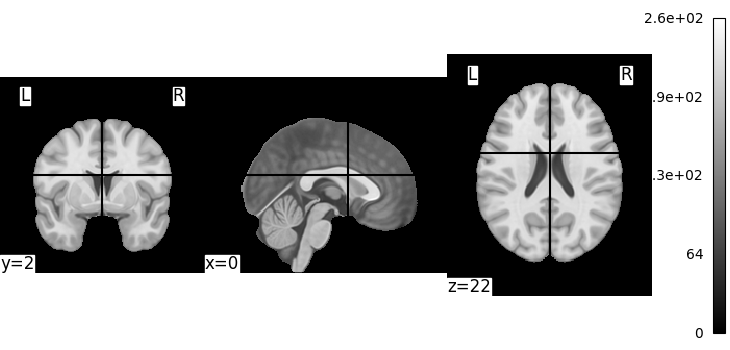

A first step: looking at our data¶

Let’s quickly plot this file:

from nilearn import plotting

plotting.plot_img(MNI152_FILE_PATH)

<nilearn.plotting.displays._slicers.OrthoSlicer object at 0x7f36fa83ab50>

This is not a very pretty plot. We just used the simplest possible code. There is a whole section of the documentation on making prettier code.